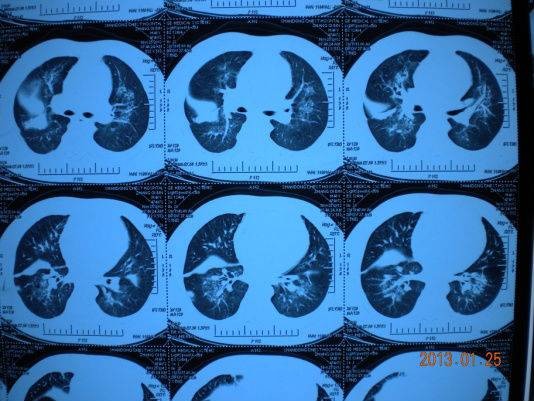

患者,张XX,男,46岁,因活动后胸闷、咳嗽2月,2012年11月11日于某省级中文av 就诊并住院治疗,胸部CT:间质性肺炎并感染,经纤支镜检查:少许纤维组织增生并慢性炎症。血抗结核抗体、支原体抗体、衣原体抗体均是阴性。以甲强龙抗炎治疗,头孢类、左氧氟沙星抗感染,后以异烟肼、利福平等抗痨治疗共半月后症状无改善,复查胸部CT病变无好转,出院。后感症状逐渐加重,于2013年1月15日入住我病区,咳嗽夜间加重,痰粘难咳,活动后胸闷,查体:双肺呼吸音粗,未及干湿罗音,舌暗苔黄,脉沉滑。心脏听诊:二尖瓣区收缩期杂音。心脏彩超示:二尖瓣脱垂,肺动脉高压,三尖瓣反流。治疗予丹红注射液30ml ivdrip qd,参芪扶正注射液250ml ivdrip qd,心先安60mg、左卡尼丁2g ivdrip qd,并以利尿剂口服。中药清热化痰、益气活血为法,方药:

以上方案治疗10天,患者症状明显改善,咳喘明显减轻,复查胸部CT:间质渗出、肺部炎症均明显吸收好转,出院。

治疗前

按:影像学出现肺部间质改变的原因很多,首先要明确病因。本例患者按特发性间质肺炎给予激素、抗生素治疗无效,后予抗结核治疗均无效。而患者心彩超示:肺动脉压高、二尖瓣脱垂,故肺内淤血水肿,易合并炎症。中西医结合治疗,改善心功能,同时配合中药清热化痰,益气活血,抗炎抗感染,减少渗出,降低肺高压。短时间内使病情明显改善。